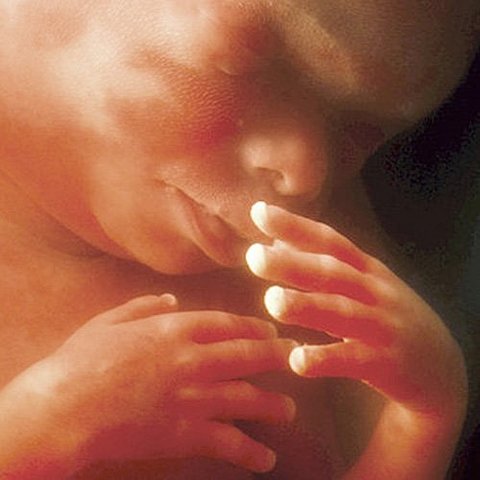

• semana 30 a 38

semana 30 a 38

El bebe ya se encuentra en la posición adecuada para el momento del parto. Su cráneo todavía no está totalmente sólido, ya que necesita pasar por el canal de parto. Al final de este período, el bebé puede alcanzar una talla de hasta 50 cm y un peso promedio de 3 kg. Hacia al final de la semana 38, el bebé está en condiciones de nacer.

• semana 39 a 40

semana 39 a 40

Durante las ultimas dos semanas se dedica a fortalecerse y ganar peso. Queda menos líquido amniótico en el útero. El vello lanugo casi ha desaparecido. El cerebro está perfectamente constituido. Puede diferenciar lo amargo de lo dulce y activar el sentido del olfato. Su corazón palpita a una velocidad de 120-160 pulsaciones por minuto. El bebé está listo para su nacimiento.